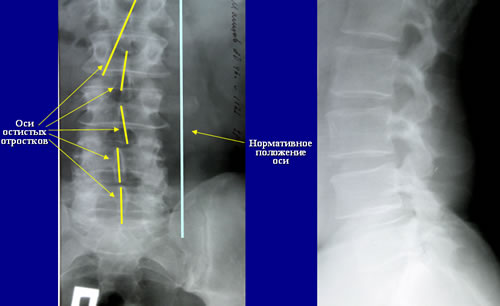

ОБСЛЕДОВАНИЕ

Рентгенологическое исследование

нижних мочевых путей (НМП)

спондилез

пояснично-крестцового отдела позвоночника, деформация

тел позвонков

Спондилез пояснично-крестцового отделов позвоночника.